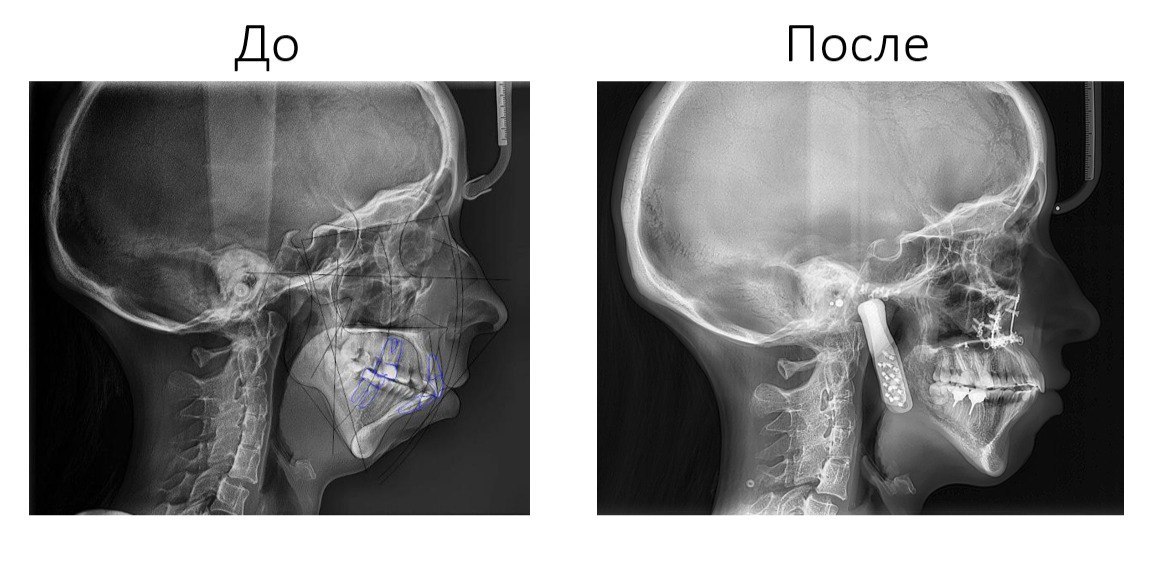

Подмосковные врачи сначала виртуально отрепетировали, а затем провели сложнейшую операцию. Они восстановили челюсть пациентке, которая не могла есть и похудела до 40 кг.

Нижняя челюсть 28-летней девушки пострадала из-за артрита — заболевания, которое поражает суставы и внутренние органы. Со временем её челюсть перестала нормально открываться, девушка даже не могла есть и при росте чуть больше 160 сантиметров похудела до 40 килограммов. Челюсть постепенно смещалась вверх, нужна была операция.

Хирурги Московского областного научно-исследовательского клинического института имени М. Ф. Владимирского взялись за сложный случай, но сначала сделали операцию виртуально: отсканировали лицо пациентки, поставили все кости в правильное положение и добавили нужные суставы.

Уже после 3D-визуализации взялись за настоящую операцию — она длилась 12 часов и прошла удачно. Девушке установили два титановых эндопротеза и восстановили прикус. Теперь она снова может улыбаться и нормально питаться.